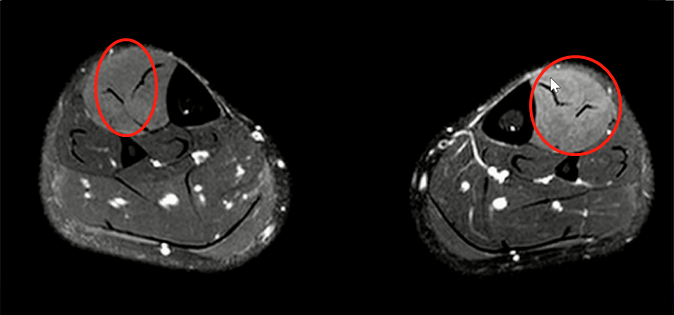

Lisfranc损伤在多发伤病人中常常容易漏诊,大约为 20-30%的漏诊率!